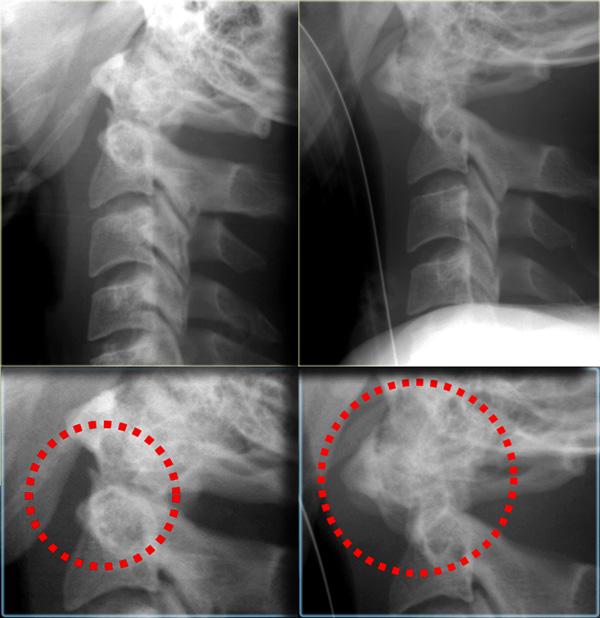

Hình bên trái là một trường hợp gãy mỏm răng loại II khác.

Đôi khi các đường gãy này có thể khó nhận thấy.

Có những hình ảnh giả gãy xương như các đường thấu quang do chồng hình (overprojection) hoặc đường Mach nổi bật (hình minh họa).